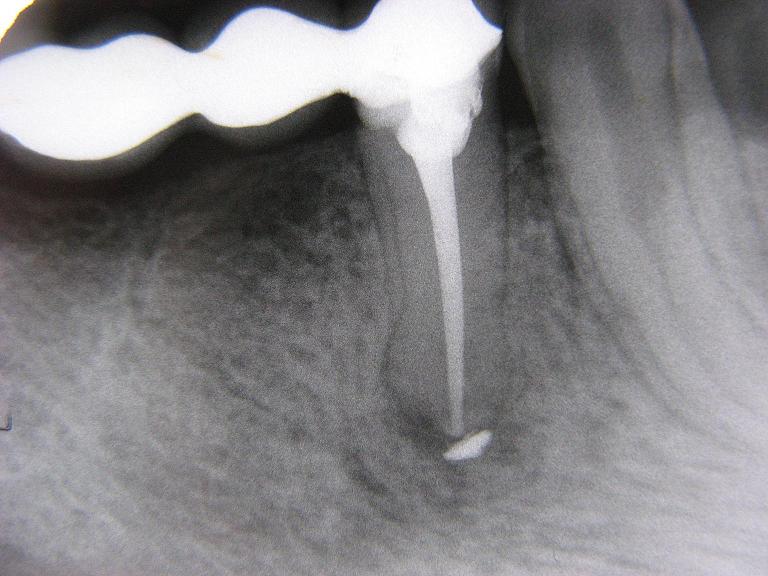

Obturatie canal cu depasire. Pentru a depasi cu succes aceste momente dureroase in aceasta perioada este indicat sa urmati un tratament cu antiinflamatorii pe cale generala. Depasirea cu material de obturatie de canal este vizibila si radiologic deci ar fi indicat sa faceti o radiografie pentru a fi siguri ca aceasta este cauza durerilor dumneavoastra. Nu dorim niciunui pacient să necesite o obturatie de canal din acest motiv accentuăm importanța profilaxiei și a unei igiene dentare sănătoase. Vizualizare 15 articole 1 la 15 din 29 în total 1 2.

Acest subiect are 28 de răspunsuri 5 voci și a fost actualizat ultima dată acum 2 ani 2 luni de dr. Salvarea de la extracția dentară. Obturatie de canal reprezinta un tratament stomatologic menit sa repare si sa salveze de la extractie un dinte infectat sau care prezinta carii dentare profunde in cadrul caruia pulpa dintelui compusa din vase de sange si nervi este extrasa. In cazul in care se intampla acest lucru obturatie de canal cu depasire cu pasta la nivel local apare o reactie inflamatorie trecatoare care se traduce prin dureri la nivelul dintelui in momentul atingerii acestuia.